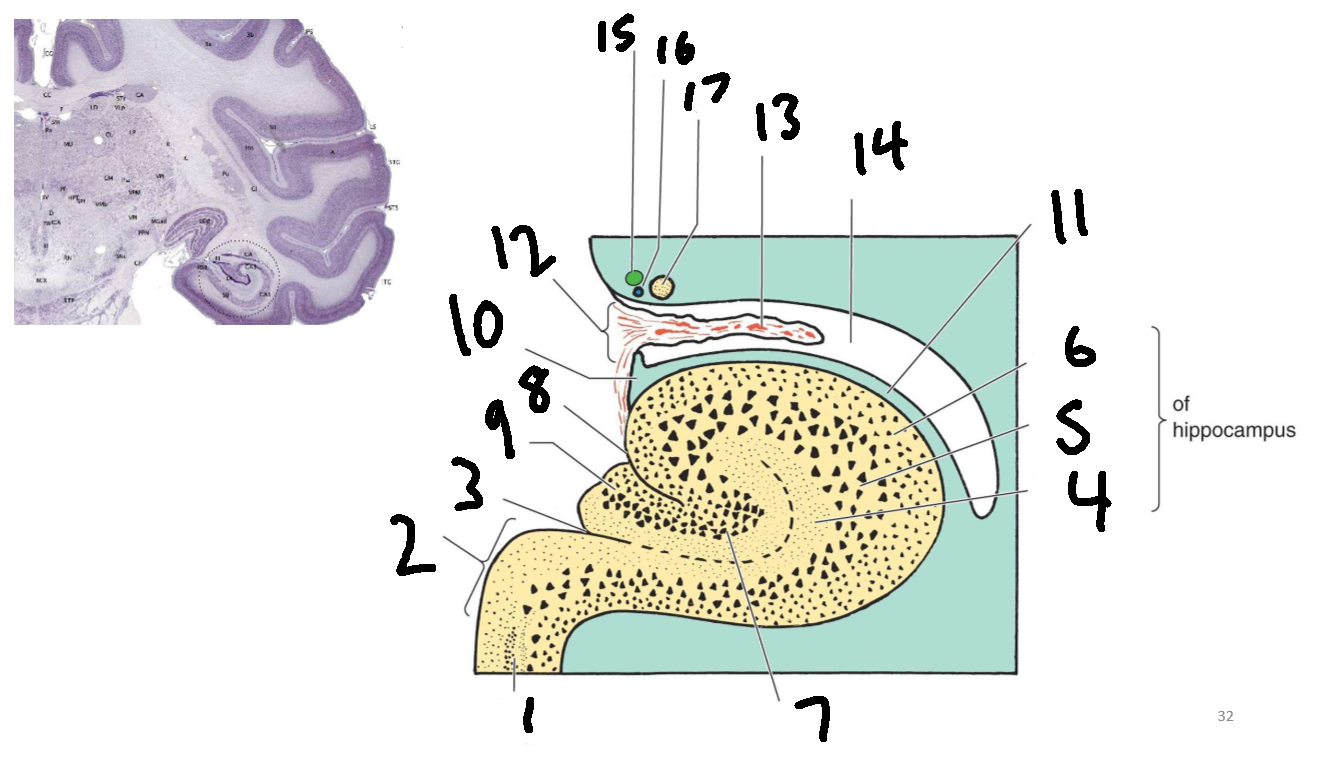

What structure is this?

hippocampus

What is 1?

hippocampus

What is 2?

rhinal sulcus

What is 3?

lateral ventricle

What is 4?

thalamus

What is 5?

entorhinal cortex

What is 6?

perirhinal cortex

What is 7?

parahippocampal cortex

What is 1?

gyrus dentatus

What is 2?

cornu ammonis

What is 3?

fimbria

What is 3’?

alveus

What is the arrow pointing to?

happicampal sulcus

What is ca1, ca2, ca3 and ca4?

fields of cornu ammonis

What is 4?

tela choroidea

What is 5?

stria terminalis

What is 6?

tail of caudate nucleus

What is 7?

temporal horn of lateral ventricle

What is 8?

collateral eminence

What is 9?

collateral sulcus

What is 10?

parahippocampal

What is 11?

entorhinal area

What is 12?

subiculum

What is 13?

lateral geniculate body

What is 1?

parahippocampal gyrus

What is 2?

subiculum

What is 3?

hippocampal sulcus

What is 4?

molecular layer

What is 5?

pyramidal layer

What is 6?

polymorphic cell layer

What is 7?

granule cell layer of dentate gyrus

What is 8?

fimbriodentate sulcus

What is 9?

dentate gyrus

What is 10?

fimbria of hippocampus

What is 11?

alveus

What is 12?

choroid fissure

What is 13?

choroid plexus

What is 14?

temporal horn of lateral ventricle

What is 15?

stria terminalis

What is 16?

thalamostriate vein

What is 17?

tail of caudate nucleus